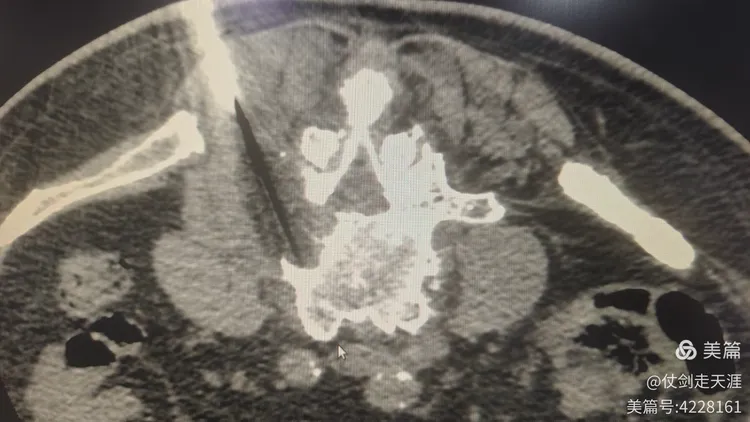

患者肺癌晚期发生腰椎转移,腰部及腿部每天都感觉剧烈疼痛,不能下床,经治疗团队讨论后最终制定了氩氦刀冷冻消融方案。手术过程中,介入治疗科副主任医师范利斌在CT引导下将氩氦刀精准插入腰椎椎体病灶,通过快速冷冻和复温,成功地将肿瘤组织摧毁,同时最大限度地保护了周围正常组织。术后第二天,患者腰腿部疼痛明显缓解。